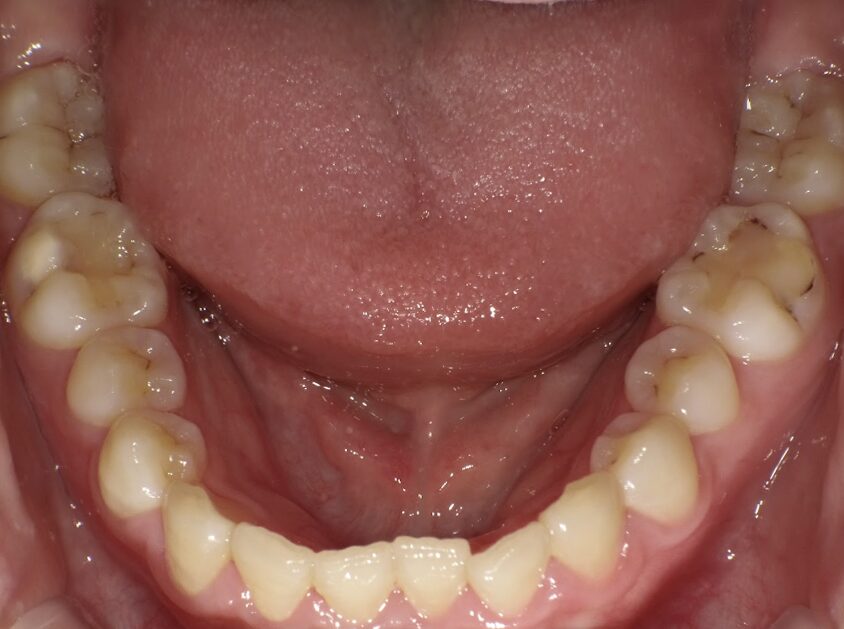

治療前

前歯のすき間が気になるを主訴に当院を受診され、前歯部空隙歯列(歯と歯の間に隙間が空いている状態)・過蓋咬合(上の歯が下の歯を深く覆いかぶさっている状態)・下顎前歯叢生(ガタガタ)を認めました。